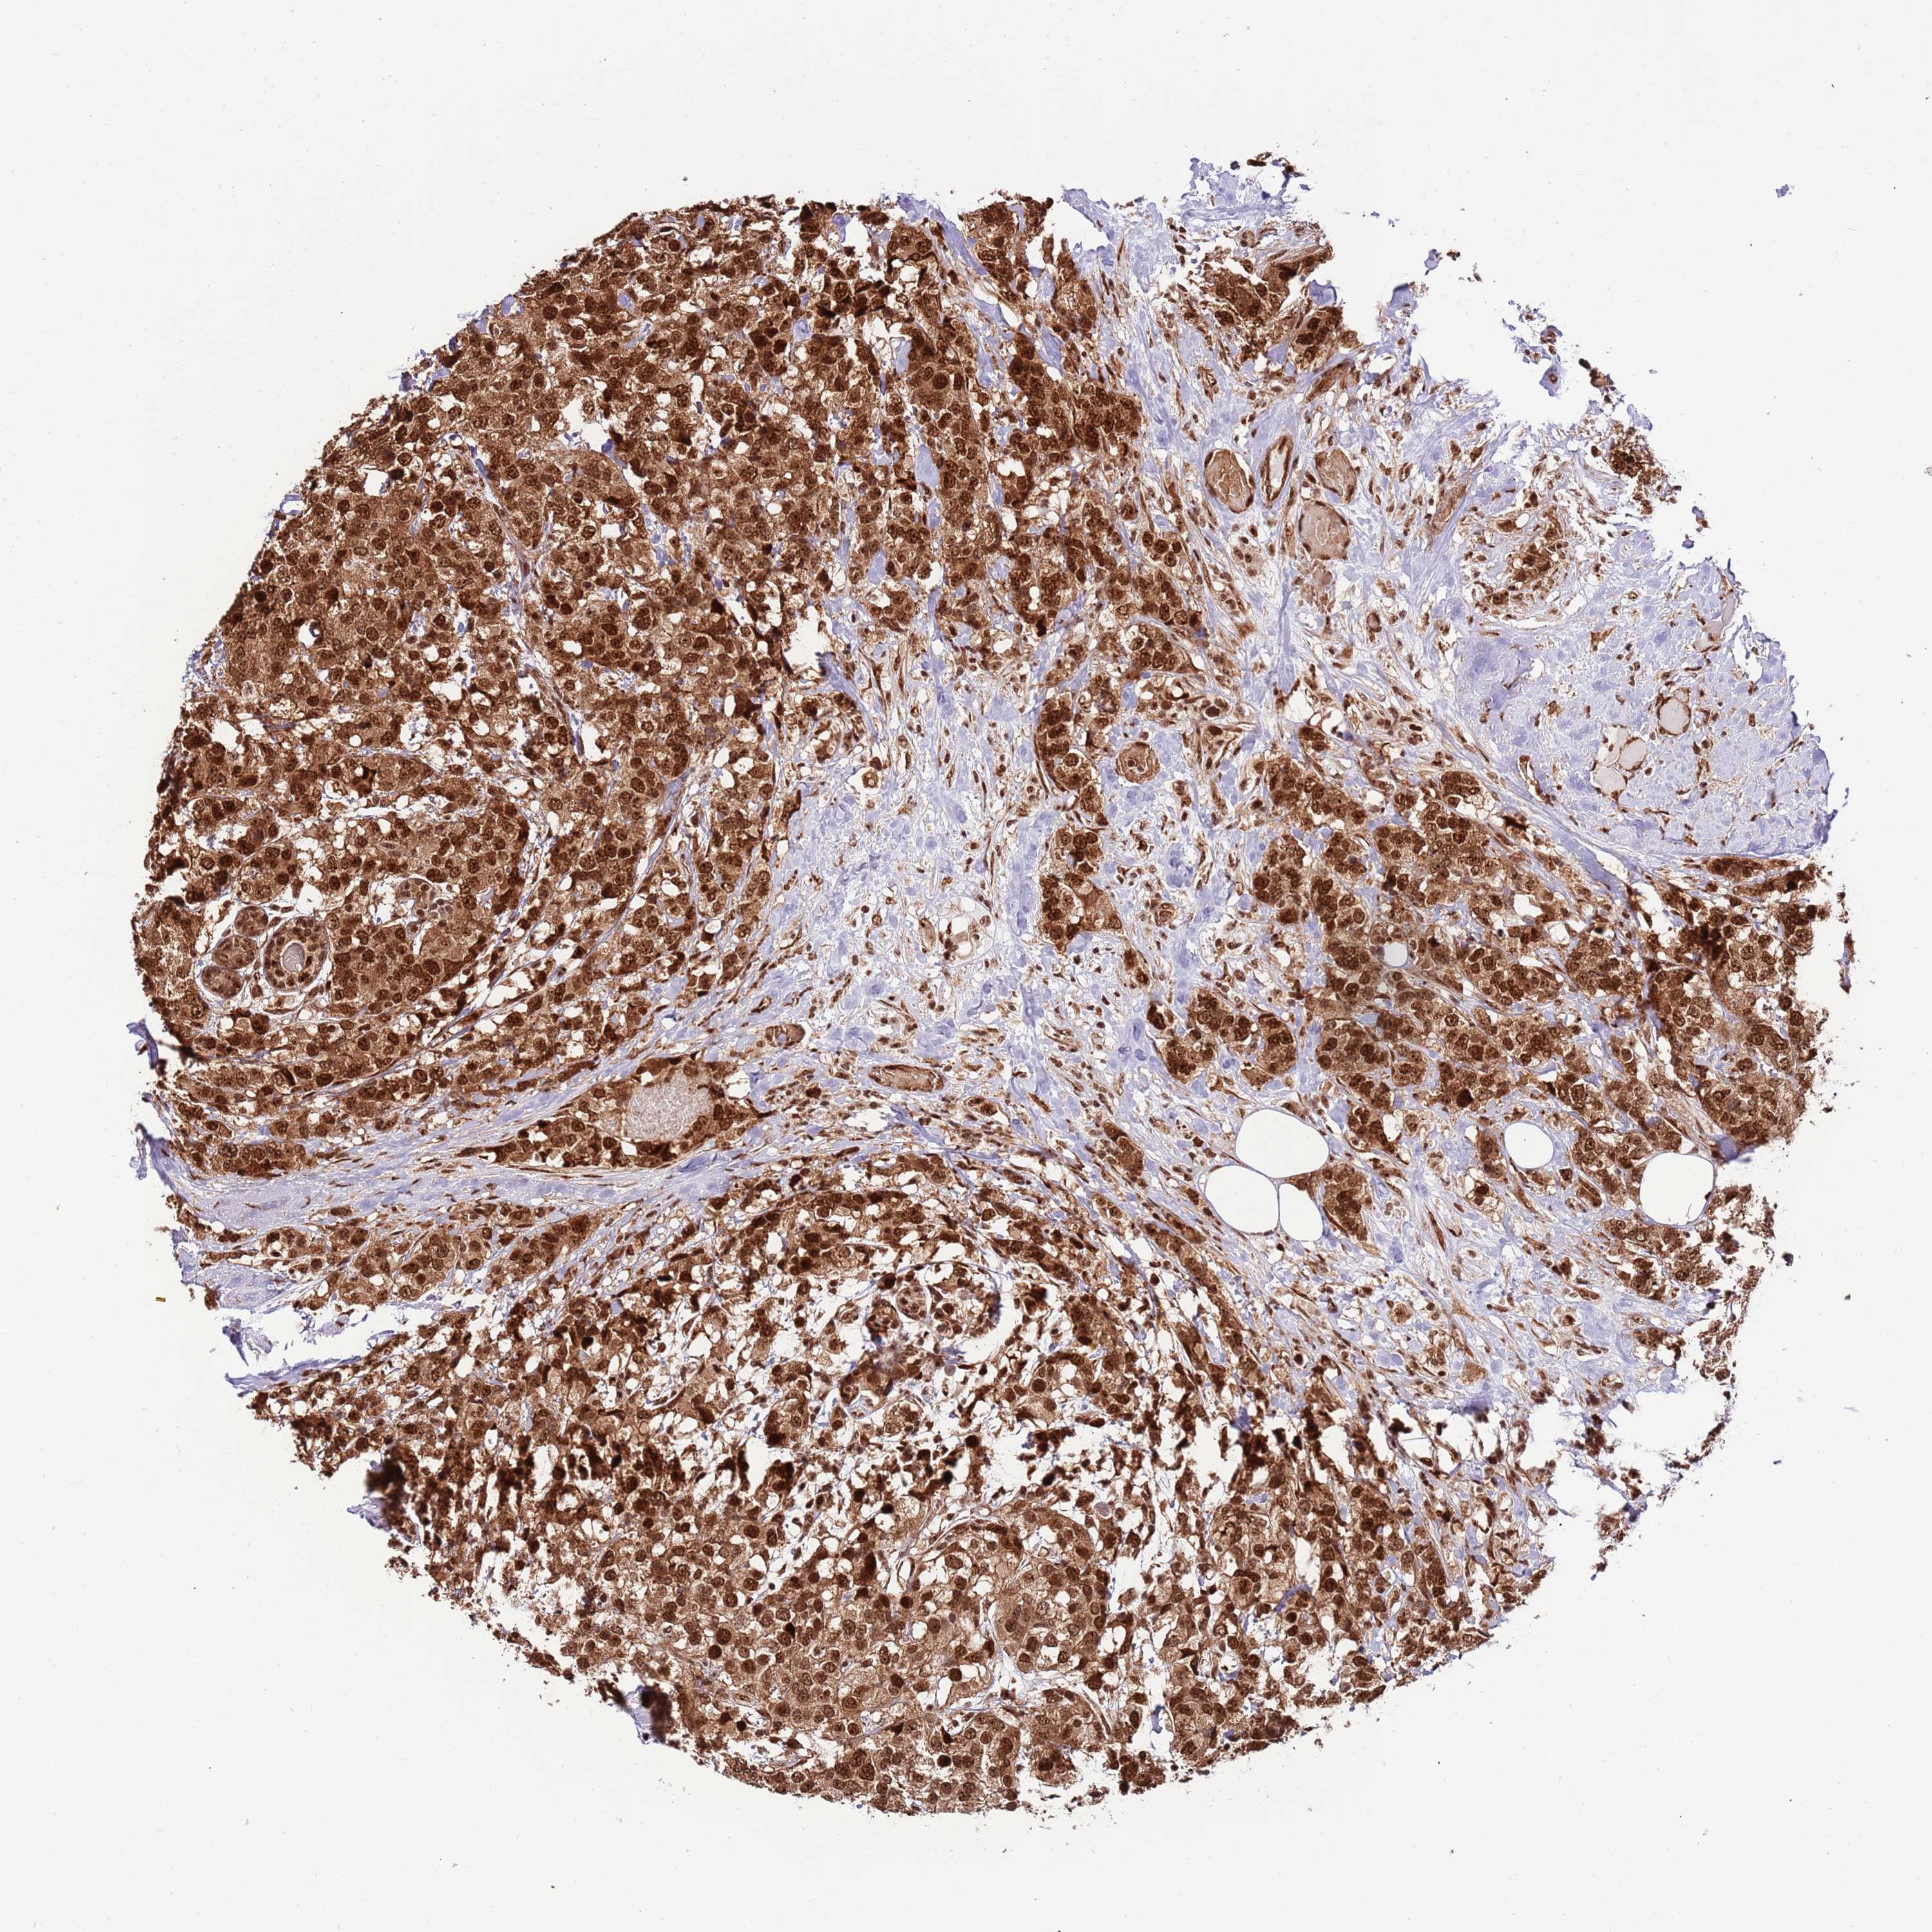

CANCER BREAST CANCER Show tissue menu

BRCA TCGA BRCA VALIDATION PROTEIN EXPRESSION